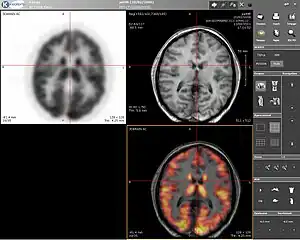

Computer screenshot showing a PET image (upper left), MRI image (upper right) and the combined PET-MRI image where PET data is overlaid over the MRI data (lower right)

Positron emission tomography–magnetic resonance imaging (PET–MRI) is a hybrid imaging technology that incorporates magnetic resonance imaging (MRI) soft tissue morphological imaging and positron emission tomography (PET) functional imaging.[1]